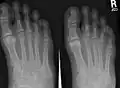

X-ray of foot.